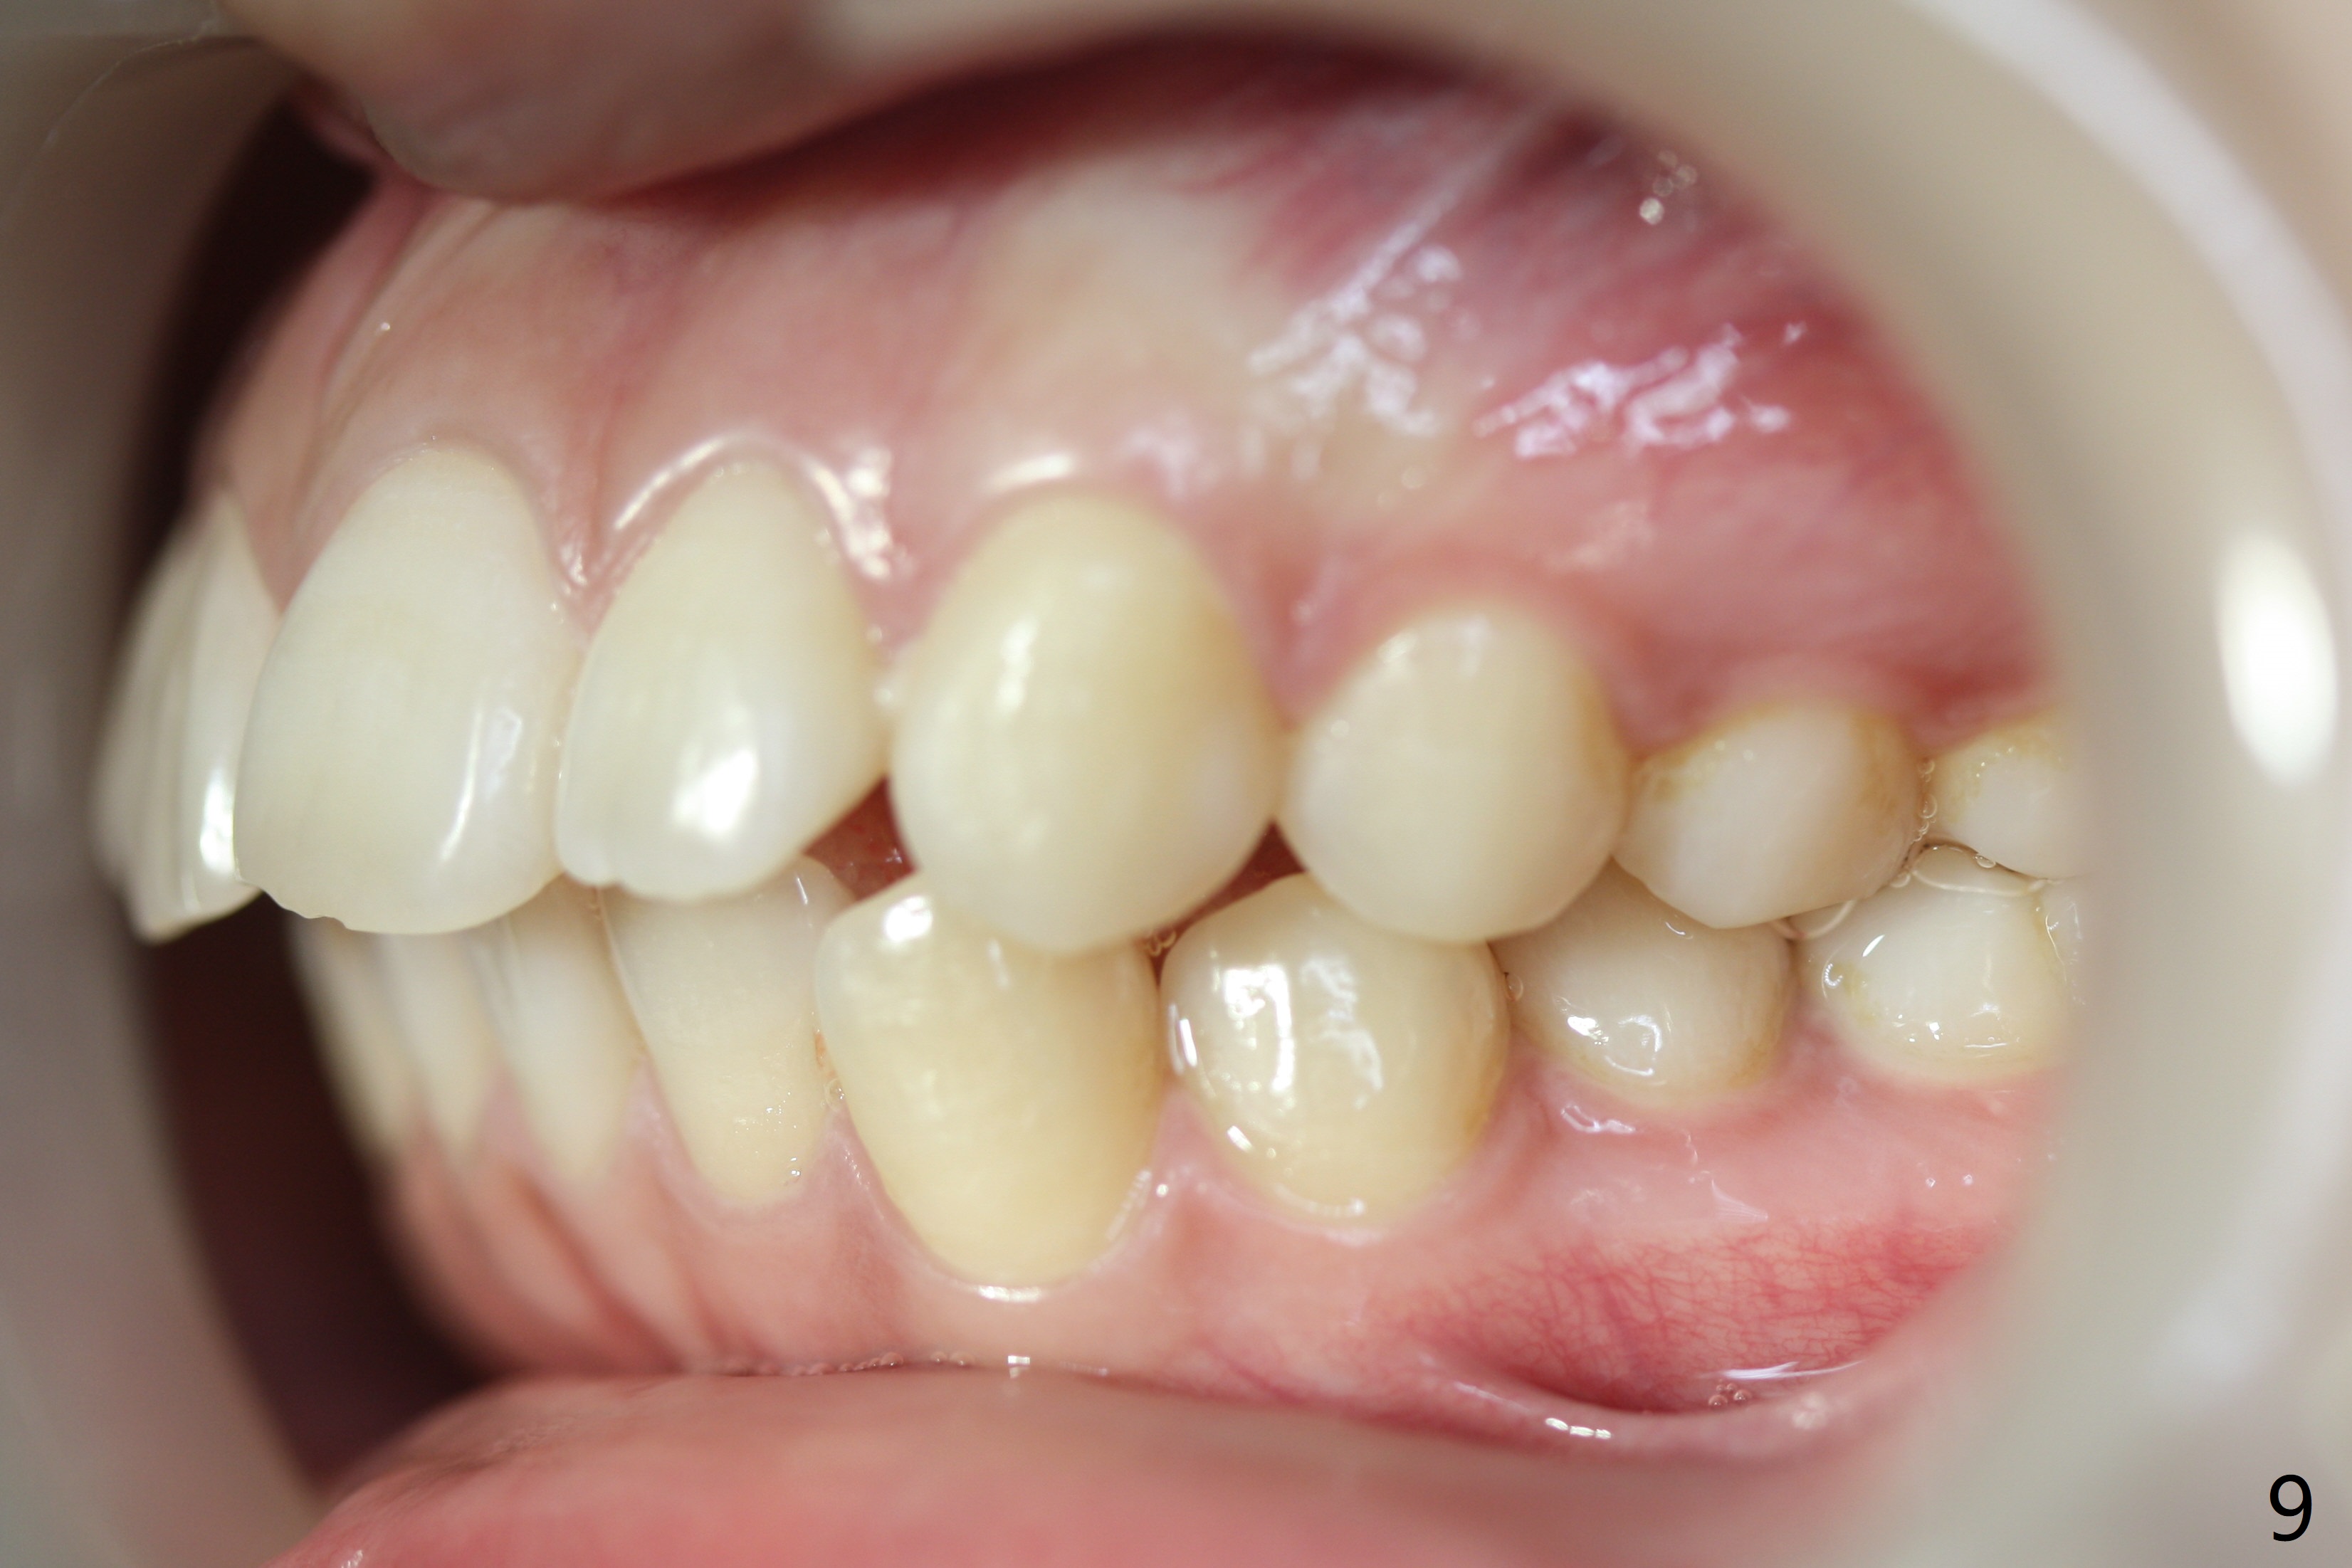

A 15-year-old woman has protrusive lips and retrusive chin (Fig.1-6). Canines and molars have Class I occlusion (Fig.7-9). With 4 bi extraction and 5-7 anchorage (Fig.10-12), 3s will be distalized after 16x16 wires, followed by posted wire retraction of 4 incisors.